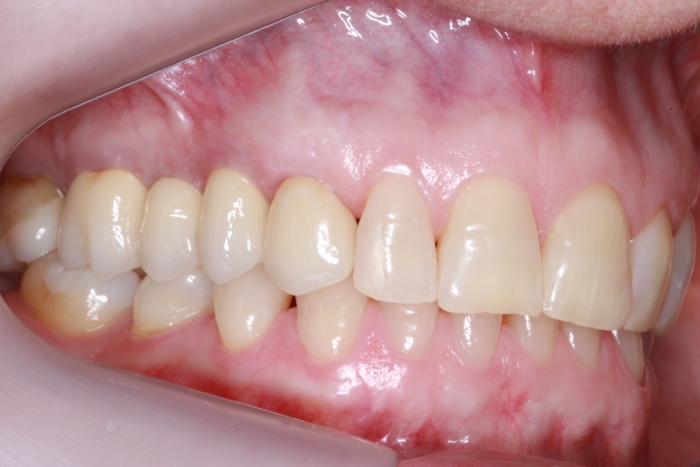

Foto lateral pré-cirurgica 03-10-16 - Clínica Cliniface

Foto lateral pré-cirurgica 03-10-16